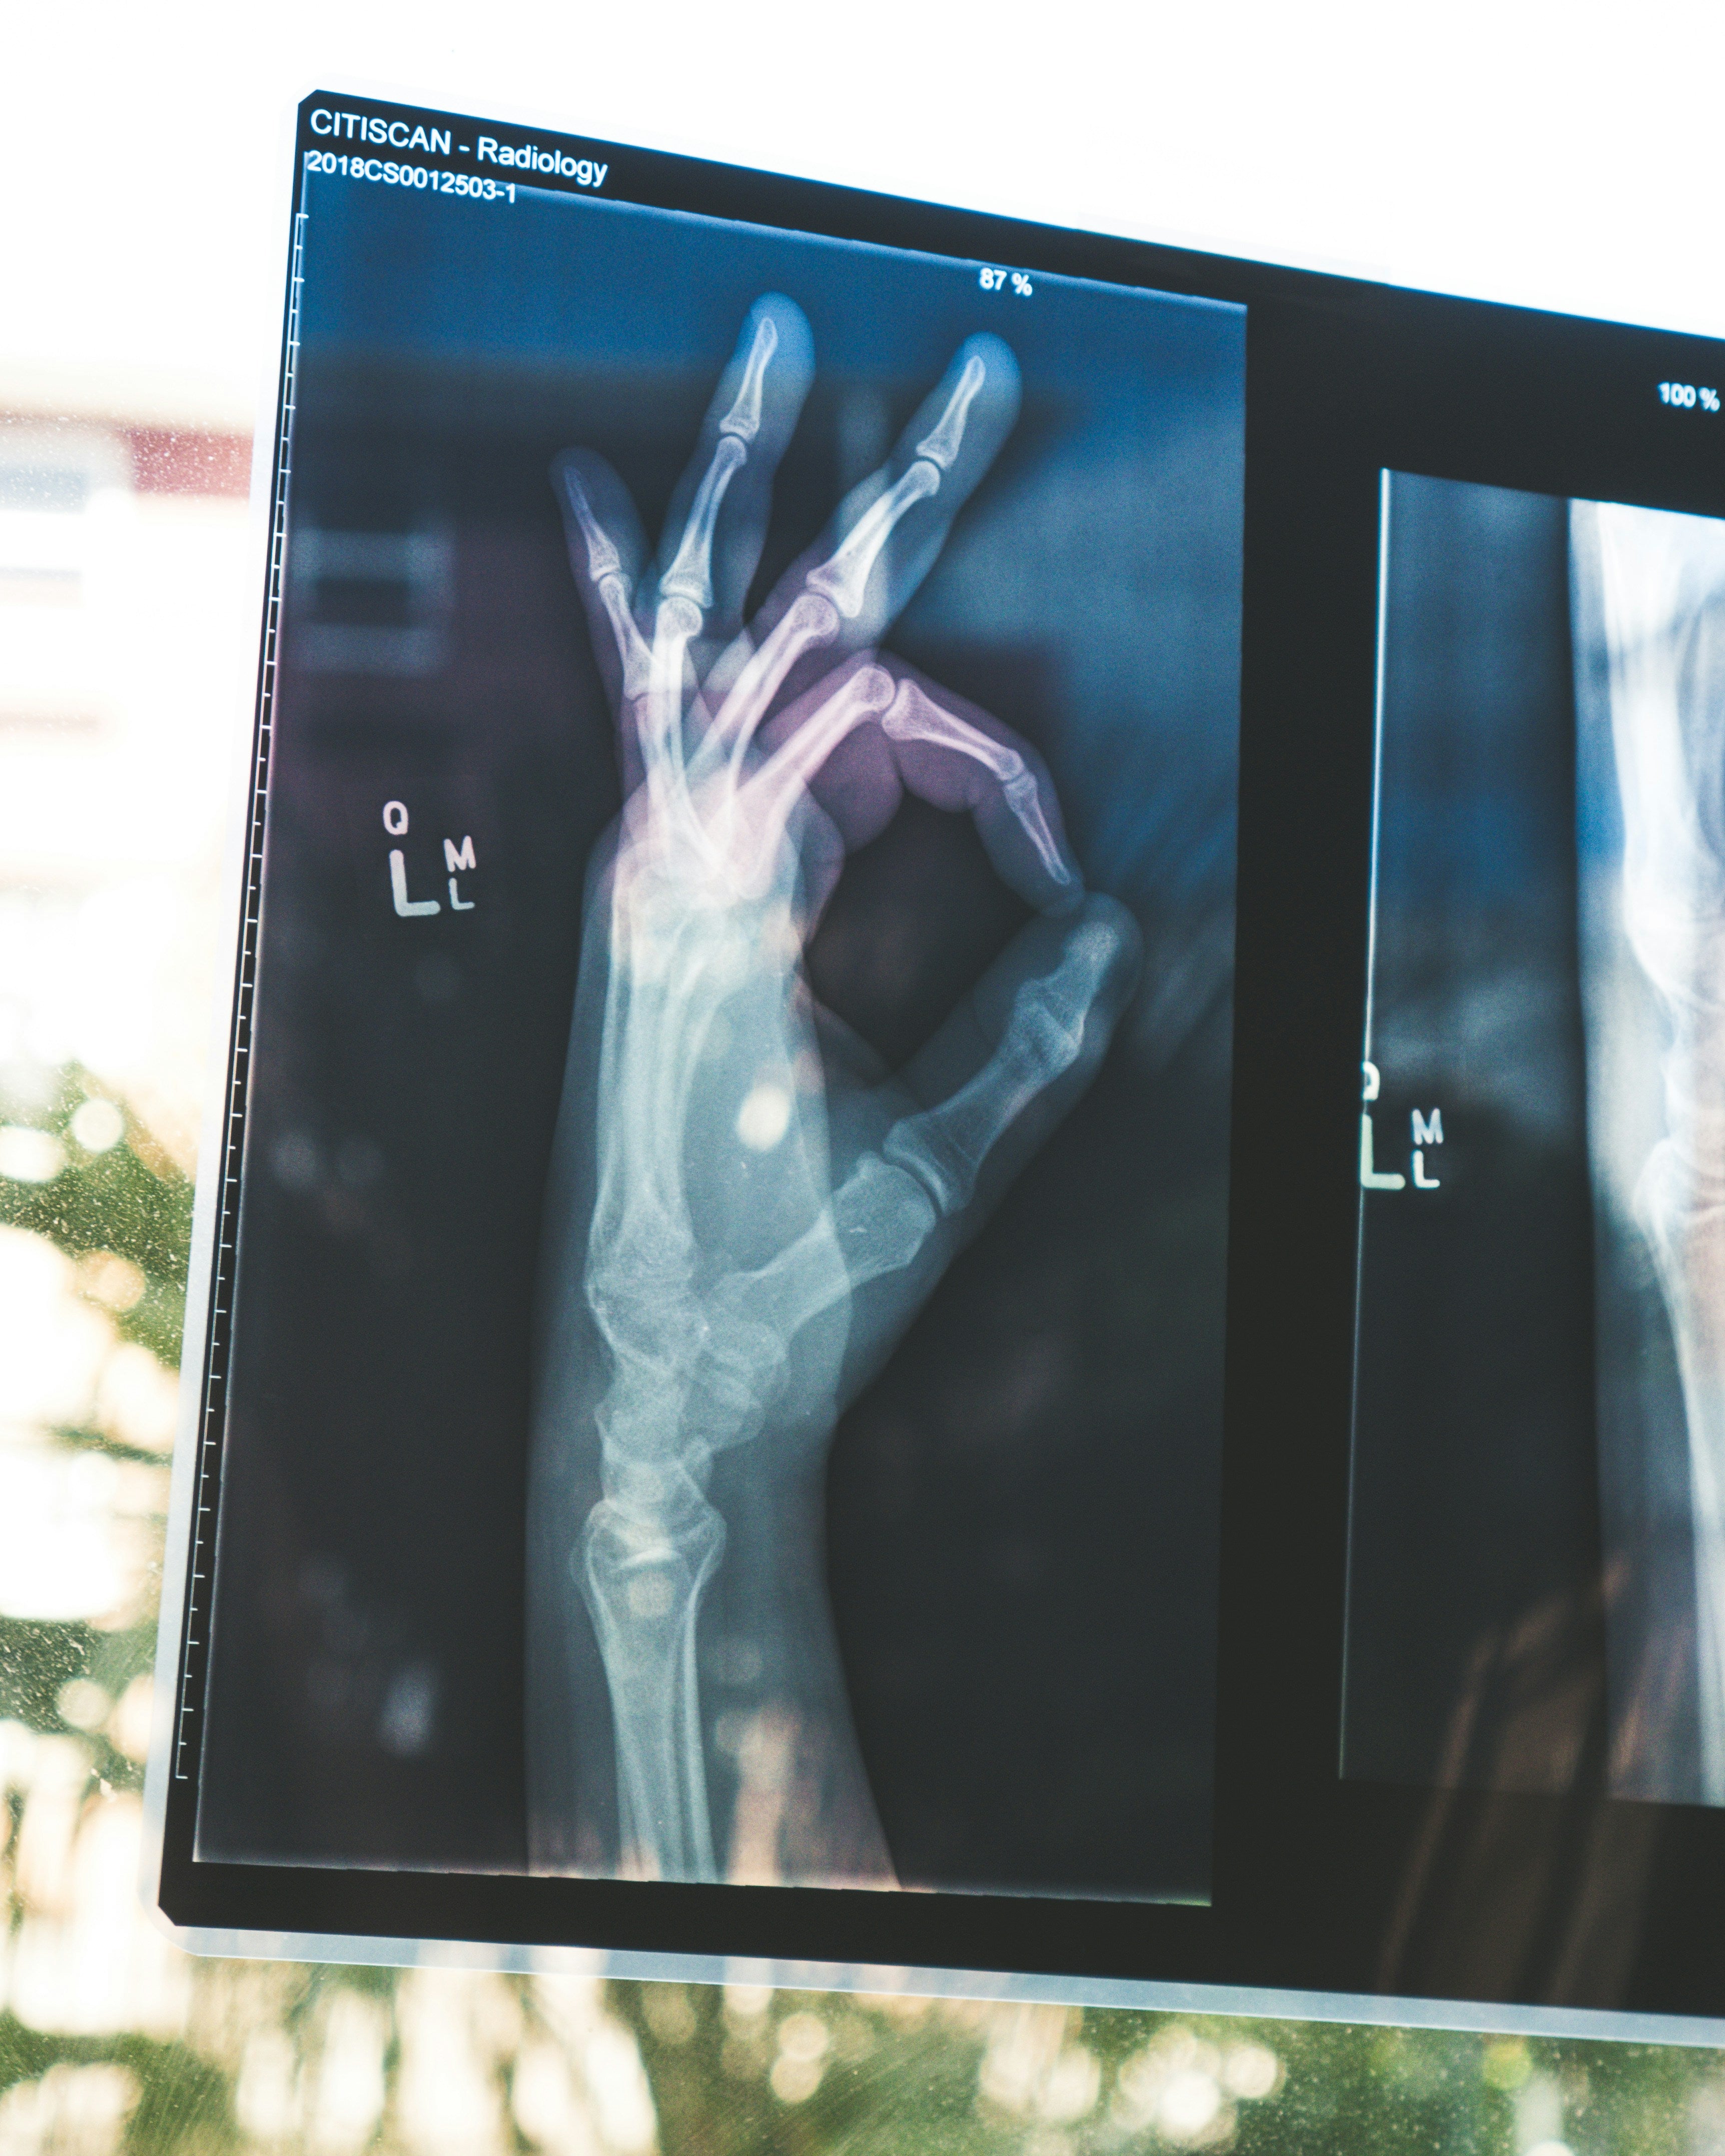

Bone Density Test

Your bones are the foundation of your body’s strength. A bone density test can help detect osteoporosis early, or if your risk of developing osteoporosis in the future is higher than average. People living with osteoporosis have porous, fragile bones, which can lead to an increase risk of bone fractures.

We want to ensure you stay strong and active, and maintain that fabulous, unstoppable you.